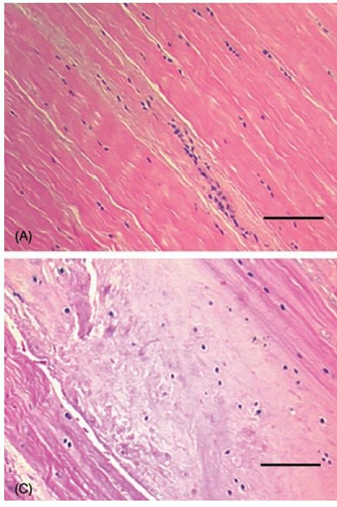

H&E stains of normal CCr and Ruptured CCr as reference

H&E Stain of ruptured CCR in study

Tissue-Level Controls

Samples were obtained only from clinically indicated surgical cases.

A histologically normal cruciate control group was not included because:

- Invasive sampling of healthy cruciate ligaments is not ethically justified

- There is no clinical indication for routine sampling of intact ligaments

Accordingly, the study design was case-referenced rather than case–control at tissue level.

This supports the discussion of correlation but does not allow inference about marker absence in normal tissue.